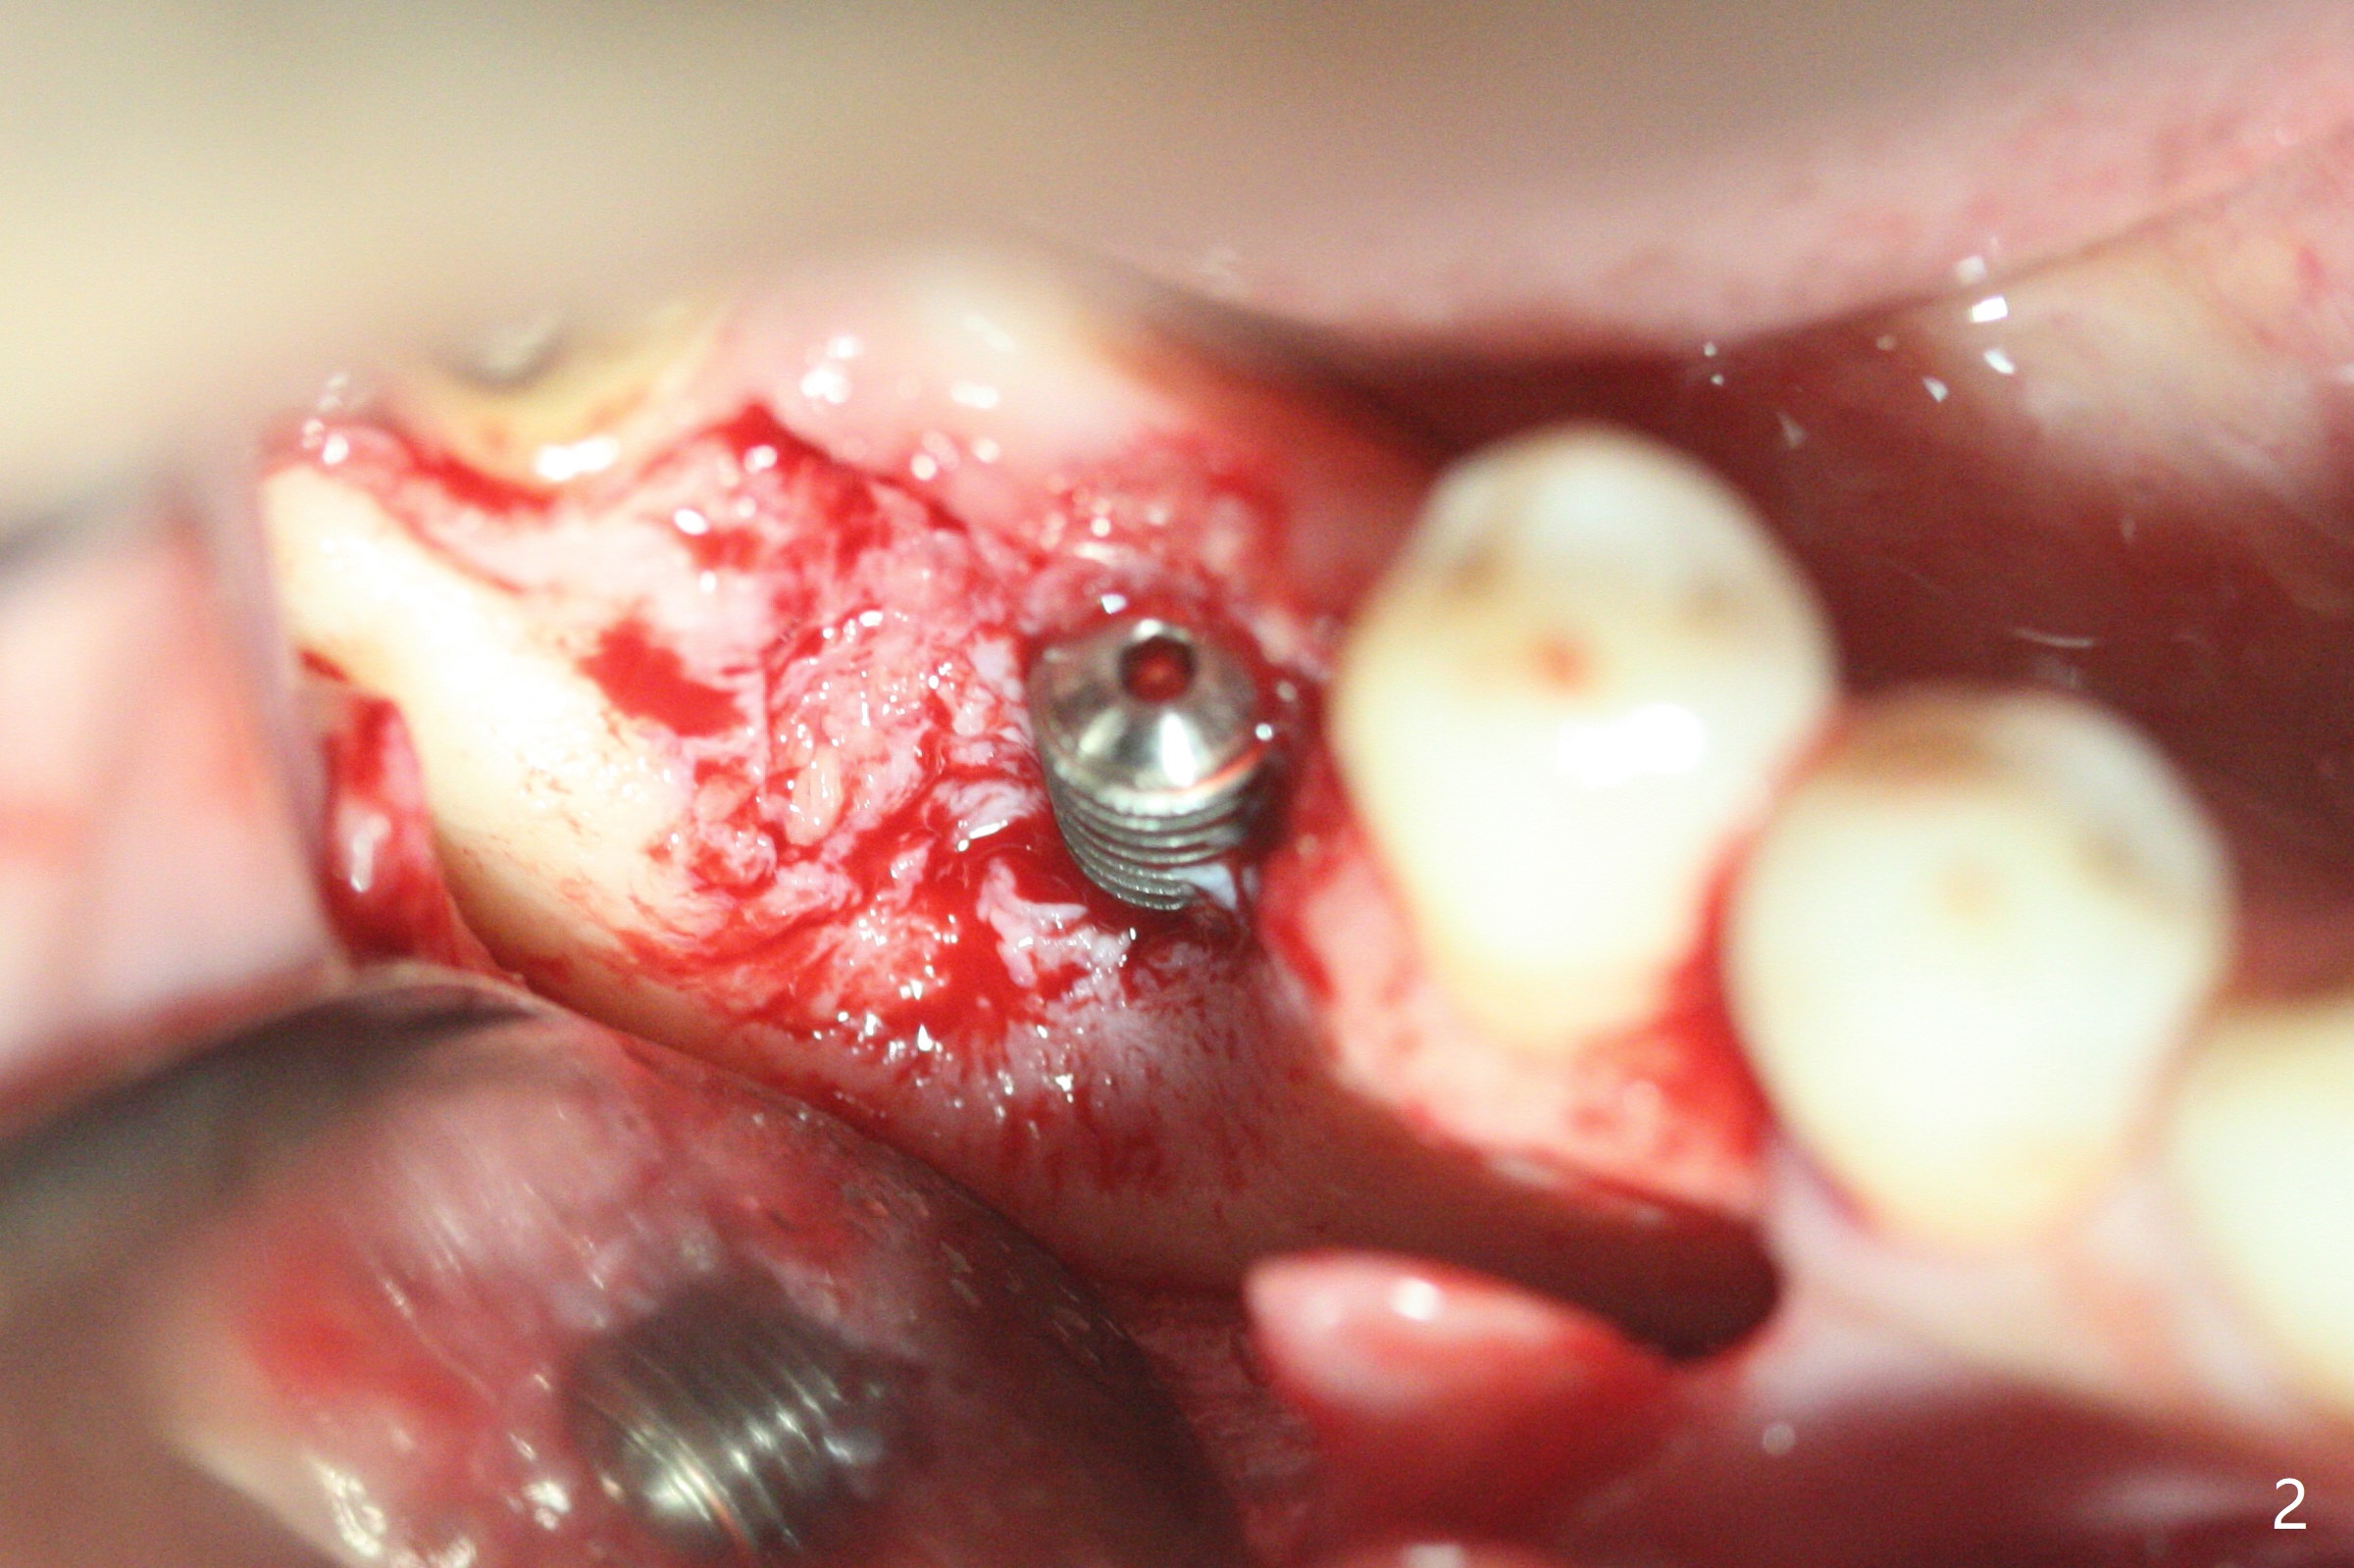

In spite of use of water pik, the coronal threads of the implant at #30 remain exposed 2 months postop (Fig.1). Envelop incision with mesial and distal accessory release ones reveals buccal bony defect (Fig.2). After 2nd spin (1500 RPM for 10 minutes), PRF forms in the red tube (Fig.3 yellow gel-like). Following use of Titanium brush, sticky bone is place (not so bone block-like, Fig.4), followed by a large piece of PRF membrane (from the red tube of Fig.3), Cytoplast (Fig.5,6 white porous) and a small piece of PRF membrane (from the white tube, next to the thin gingiva). The distal (Fig.6 D) and mesial (Fig.7 M) flaps are approximated (arrows without suture) as much as possible as well as lingual. 4-0 Polyglycolic Acid suture is used. Periodontal dressing dislodges 5 days postop. When the patient returns 1 week postop, he is pain free. Although Cytoplast is exposed, the surrounding gingiva seems to be healthy (Fig.8). Later the permanent crown of #31 is temporarily cemented with OHI. It appears that Cytoplast could be used to cover PRF membranes for soft tissue defect, followed by immediate provisional at the stage of immediate implant. The discolored (apparently contaminated) Cytoplast seems to be expelled 6 weeks postop (Fig.9). When the latter is removed, the soft tissue looks normal (Fig.10). Two weeks later, the apparently normal, but thin gingiva forms over the former granulation tissue (Fig.11 *, as compared to Fig.10). There is not enough bone coronal to the implant plateau 2 months post graft (Fig.12). Three months later, bone graft will be re-placed possibly with uncover.